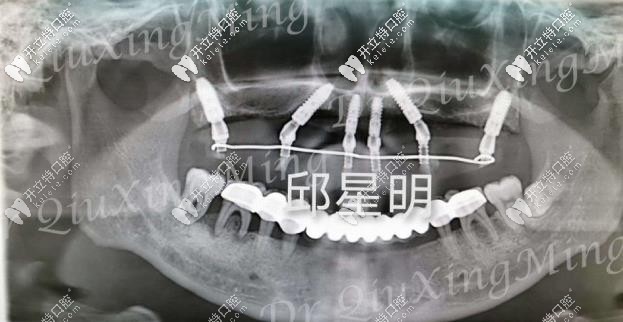

植入種植體的牙片

種植過程也挺快的,大約用了兩個(gè)多小時(shí),六根植體就已經(jīng)植入進(jìn)去了,然后需要等2-3個(gè)月的牙床恢復(fù)期,才能安裝基臺(tái)和牙冠。這段時(shí)間只需安心等待就好了!